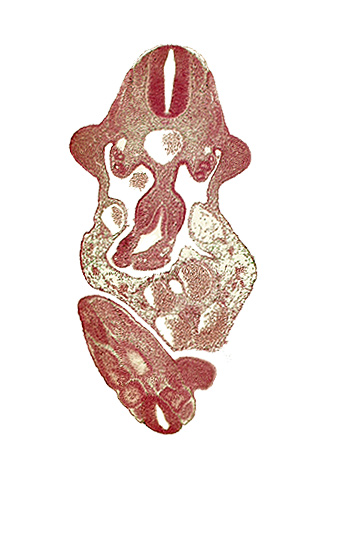

Carnegie Embryo #836 | Location: 10-02-04

Keywords: C-7 spinal ganglion primordium, aorta, caudal edge of cloaca, caudal eminence, caudal end of neural tube, coelomic cavity, dermatomyotome 11 (C-7), floor plate, junction of midgut and omphalo-enteric duct, left umbilical artery, left umbilical vein, lower limb bud, mesonephric duct, mesonephros, roof plate, somite 30 (S-1), somite 31 (S-2), sulcus limitans, upper limb bud

Source: The Virtual Human Embryo.